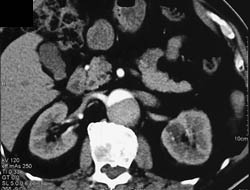

Aortic Dissection